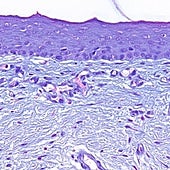

Fina y transparente, casi se puede ver a través de ella. Esta es solo una de sus muchas virtudes que la han convertido en un recurso esencial para la oftalmología, entre otras muchas especialidades.

La placenta es el único órgano efímero del organismo humano. Durante la gestación, proporciona al feto los nutrientes y anticuerpos necesarios para su desarrollo y le protege frente a infecciones y toxinas. Tras el alumbramiento, sigue teniendo valor por su riqueza en células madre, colágeno y citoquinas que la convierten en un tejido único para la medicina. Sobre todo, su capa más interna.

La membrana amniótica posee características bioquímicas y mecánicas esenciales para el tratamiento de quemaduras y úlceras oculares, o cuando las heridas de la piel nunca curan. Pero, cada vez más, es un recurso único en cirugía, en especialidades tan distintas como la ginecología, la urología, la neurocirugía o la cirugía ortopédica.